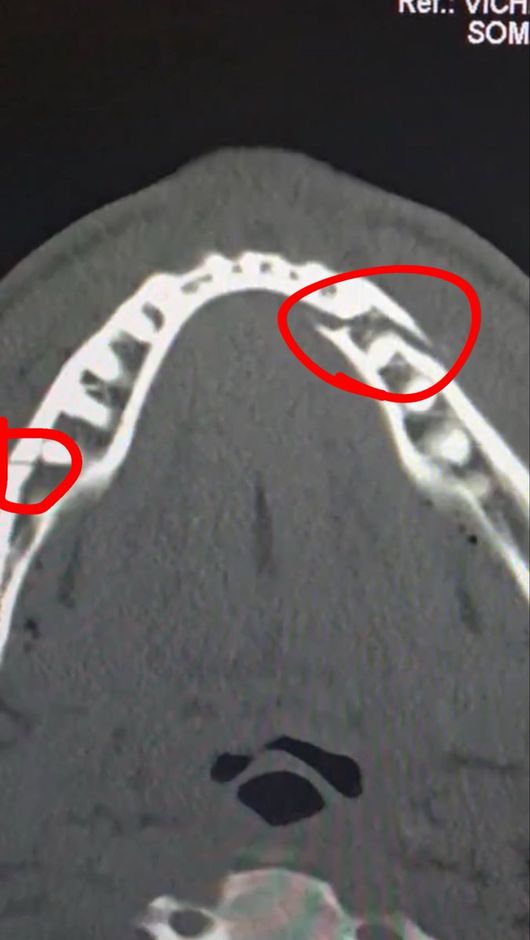

턱뼈 부러지게 맞고 '1370억' 초대박! 유튜버 출신 복서, 또 깜짝 선언..."조슈아와 100% 다시 싸울 것" 훈련 시작했다